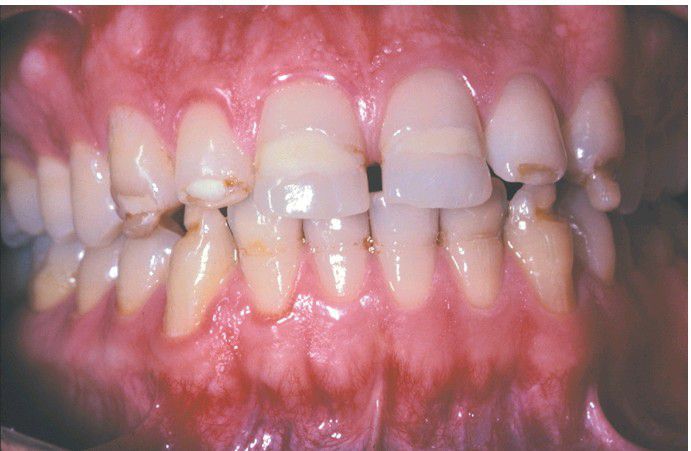

Environmental enamel hypoplasia

Bilaterally symmetrical pattern of horizontal enamel hypoplasia of the anterior dentition. Maxillary central incisors have been restored previously